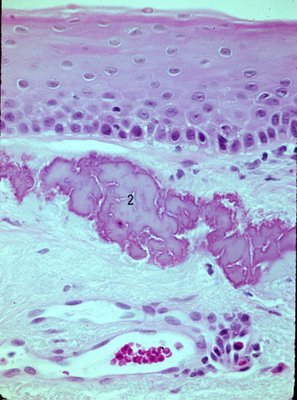

🧬 Histopathology

- Hyaline material deposits beneath the epithelium

- Extends to Bowman’s layer and stromal matrix in advanced stages